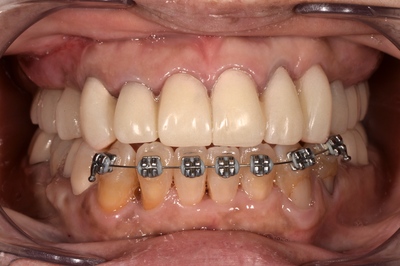

治療開始1年、3回目のプロビジョナルクラウンが装着された様子。

D41_3607.JPG

細かいところの治療はまだまだ続く、、、、、